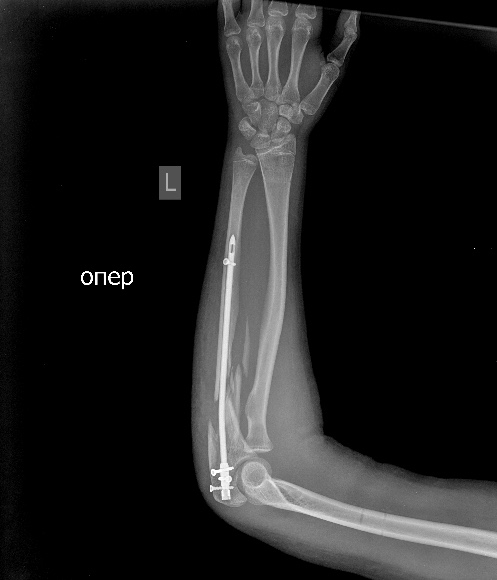

[Ortho] псевдоартроз локтевой с застарелым вывихом радиоульнарного сочленения

Мы бы удалили пластину.  Аппаратом постепенно восстановили бы

взаимоотношения. И заштифтовали бы локтевую кость, смоделировав

стержень, чтобы он был напряжен в противоположную сторону тому, как

сейчас выглядит локтевая кость, т.е. вогнутой стороной в торону

межкостного промежутка. Чтобы лучевая кость удерживалась натяжением

межкостной мембраны. Пример в приложении. Тут был более свежий случай,

поэтому вправилось одномоментно.

Имя     : 2Предплечье AP.0001.jpg

Тип     : image/jpeg

Размер  : 51201 байтов

Url     : http://weborto.net:8080/pipermail/ortho/attachments/20141104/6ce4852a/attachment-0005.jpg